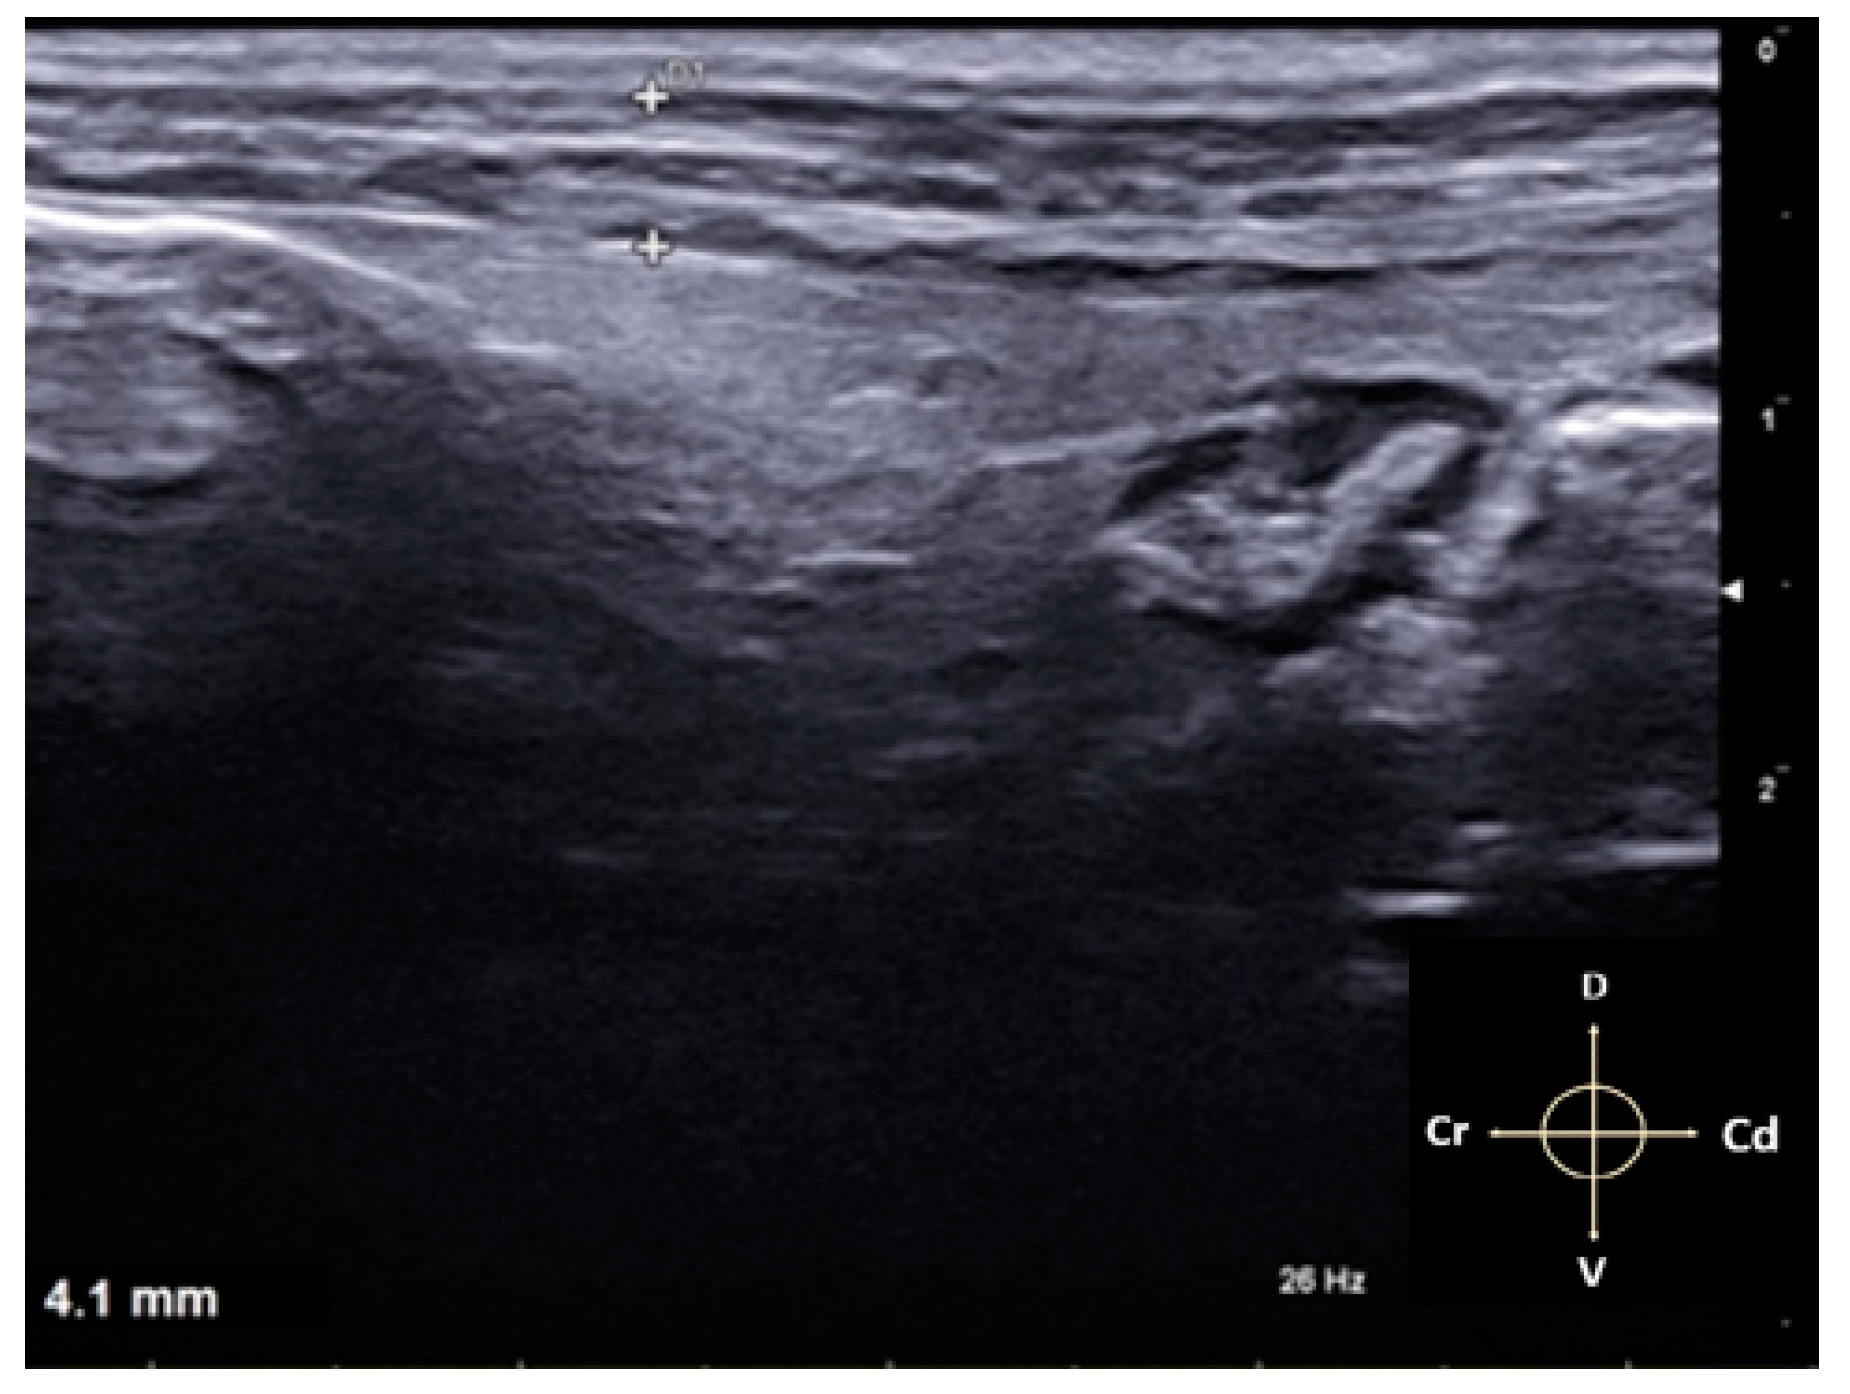

2.1. US-Guided TAP Block

3.1. US-Guided TAP Block